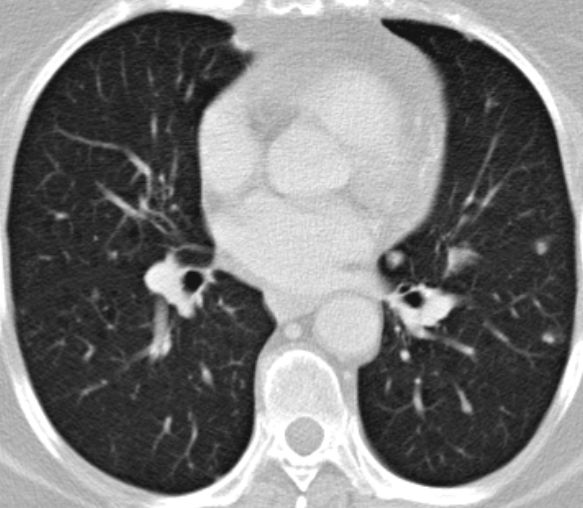

| Metastasierung | Lungenmetastasen und Lokalrezidiv 1 Jahr nach Leiomyosarkom der rechten Beckenwand.

![]() | ||